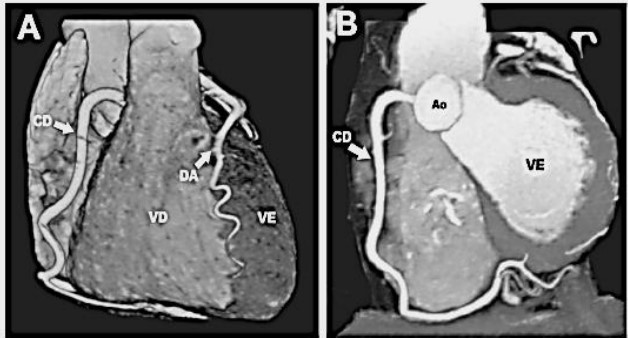

Observe as Imagens ilustrativas de um paciente que foi submetido à angiotomografia coronariana. Neste caso, a angiotomografia foi inteiramente normal, excluindo a presença de doença da artéria coronária (DAC). Pode ser visto o ventrículo direito (VD) e o ventrículo esquerdo (VE). O tipo de sangue que “chega” no VE e o vaso que conduz o sangue durante a sístole deste ventrículo em direção dos tecidos pode ser encontrado na opção: